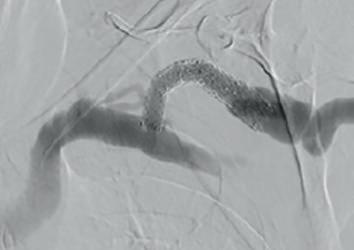

Example procedural outcome: treatment of Bond’s patient with a left brachiocephalic AVF that presented with a stenosis at the cephalic arch with aneurysmal segment.

(A) Fistulogram taken preintervention and (B) after deployment of WRAPSODY to treat. (C) Fluoroscopy of treated segment at 18 months (D) and patient’s arm at time of presentation

Jones echoes Bond’s suggestion that Wrapsody is straightforward to use. “It tracks very well through the vessel, over the wire and through the stenosis. On deployment the device remains stable, and the trigger delivery system is very responsive.”

On the device’s design, Jones highlights its unique tri-layer configuration, with its polytetrafluoroethylene (PTFE) inner layer, its cell-impermeable layer, and expanded PTFE (ePTFE) outer layer that allows it to be embedded into the vessel wall. He also cites its optimised radial strength and relative compression resistance.

“For me,” he says, “one of the most interesting design features is the softened end-rows. These are designed in a scalloped fashion with the aim of reducing stress at the interface between the edge of the stent and the normal adjacent vessel, which will hopefully reduce the incidence of edge stenosis—the Achilles’ heel of stent grafts.”